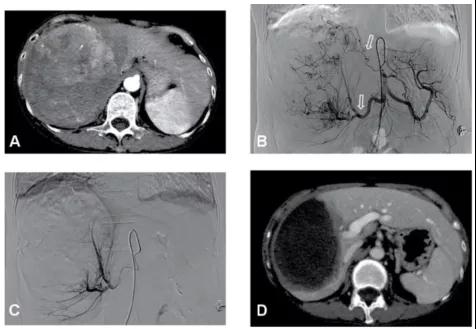

图1、病例54岁,肝右叶5.5×5.4cm肝癌(左图),行TACE+消融肿瘤完全坏死并缩小(右图),现患者已生存14年。

图4、该例肝右叶巨大肝癌合并门静脉右支癌栓(左图,箭头示癌栓),采用TACE治疗肝内肿瘤和放射性粒子治疗门静脉癌栓,术后19个月肝右叶肿瘤几乎完全坏死缩小,而粒子阻止了癌栓进展到主干,门静脉主干保持通畅(右图),现患者已生存5年。